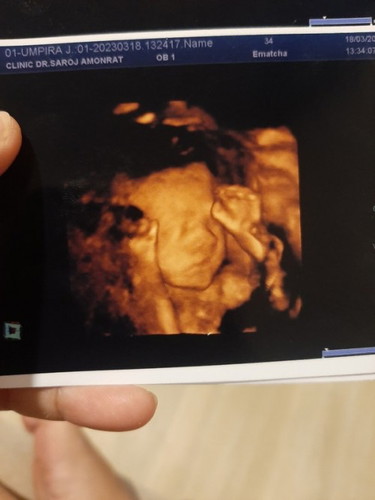

แม่ ๆ ช่วยดูให้หน่อยค่ะ ว่าปากน้องเต็มดีไหมคะ แบบนี้ปกติดีใช่ไหมคะ แม่มีความกังวลค่ะ

ขอความคิดเห็นจากแม่ๆ หน่อยค่ะ ท้องแรก แม่ค่อนข้างมีความกังวลค่ะ

หมอไม่แจ้งก็ปกติจ้า

กี่วีคค่ะแม่

27+5ค่ะ